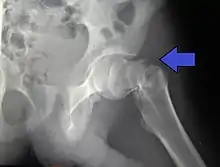

Nonunion, failure of the fracture to heal, is common in fractures of the neck of the femur, but much more rare with other types of hip fracture. Avascular necrosis of the femoral head occurs frequently (20%) in intracapsular hip fractures, because the blood supply is interrupted.[5]

For low-grade fractures (Garden types 1 and 2), standard treatment is fixation of the fracture in situ with screws or a sliding screw/plate device. This treatment can also be offered for displaced fractures after the fracture has been reduced.

In elderly patients with displaced or intracapsular fractures surgeons may decide to perform a hemiarthroplasty, replacing the broken part of the bone with a metal implant.[38] However, in elderly people who are medically well and still active, a total hip replacement may be indicated. Independently mobile older adults with hip fractures may benefit from a total hip replacement instead of hemiarthroplasty.[39]